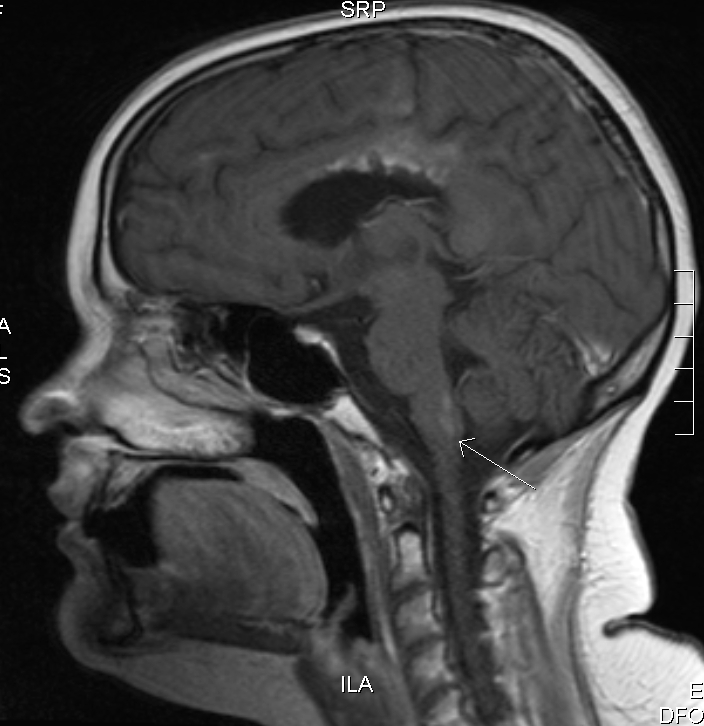

On 29 Aug 2007 Meghan had another MRI scan, after three relatively stable months. The existing tumor sites hadn’t changed since the May MRI, but there was a new kid in town: a 1.5-cm lesion on Sadie’s medulla oblongata.

Side view MRI showing brain stem lesion

29 Aug 2007: 3 months after the previous MRI, the tumor had spread into the brain stem (arrow).